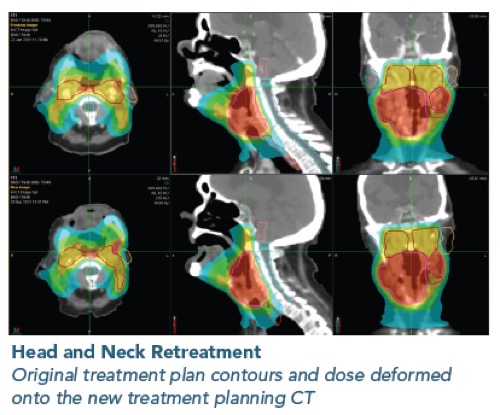

PreciseRTX™ - Για την ασφαλή χορήγηση θεραπείας σε περίπτωση επανακτινοβόλησης

Στην περίπτωση επανακτινοβόλησης, το σύστημα PrecisionRTX επιτρέπει την εισαγωγή των δεδομένων από προηγούμενες θεραπείες και την ενσωμάτωση τους στο νέο πλάνο ακτινοθεραπείας.

Στην περίπτωση επανακτινοβόλησης, το σύστημα PrecisionRTX επιτρέπει την εισαγωγή των δεδομένων από προηγούμενες θεραπείες και την ενσωμάτωση τους στο νέο πλάνο ακτινοθεραπείας.

Σε συνδυασμό με την ικανότητα του συστήματος TomoTherapy να δημιουργεί σύμμορφα πλάνα αποφεύγοντας κρίσιμα όργανα, το σύστημα PreciseRTX™ δίνει την δυνατότητα στους ακτινοθεραπευτές Ιατρούς να προσφέρουν ασφαλείς θεραπείες στους ασθενείς που έχουν λάβει προηγούμενες θεραπείες με ακτινοβολία

PreciseRTX

- Επιτρέπει την εισαγωγή προηγούμενων πλάνων θεραπείας ασθενών από οποιαδήποτε άλλο σύστημα.

- Αποτελεί μια ενσωματωμένη λύση στο σύστημα σχεδιασμού θεραπείας Precision η οποία εξαλείφει την ανάγκη μεταφοράς δεδομένων μεταξύ συστημάτων διαφορετικών κατασκευαστών.

- Ευθυγραμμίζει αυτόματα τα απεικονιστικά δεδομένα και τα δεδομένα των πλάνων θεραπείας (σχεδιασμένες δομές και δοσιμετρικές κατανομές) προηγούμενων θεραπειών με τις νέες εικόνες αξονικής τομογραφίας λαμβάνοντας υπόψη μεταβολές στην ανατομία του ασθενούς (Deformable registration)

- Αθροίζει τις κατανομές δόσης των προηγούμενων θεραπειών με την κατανομή δόσης του νέου πλάνου θεραπείας.

- Περιλαμβάνει εργαλεία αξιολόγησης των συνολικών και των επιμέρους δοσιμετρικών κατανομών.